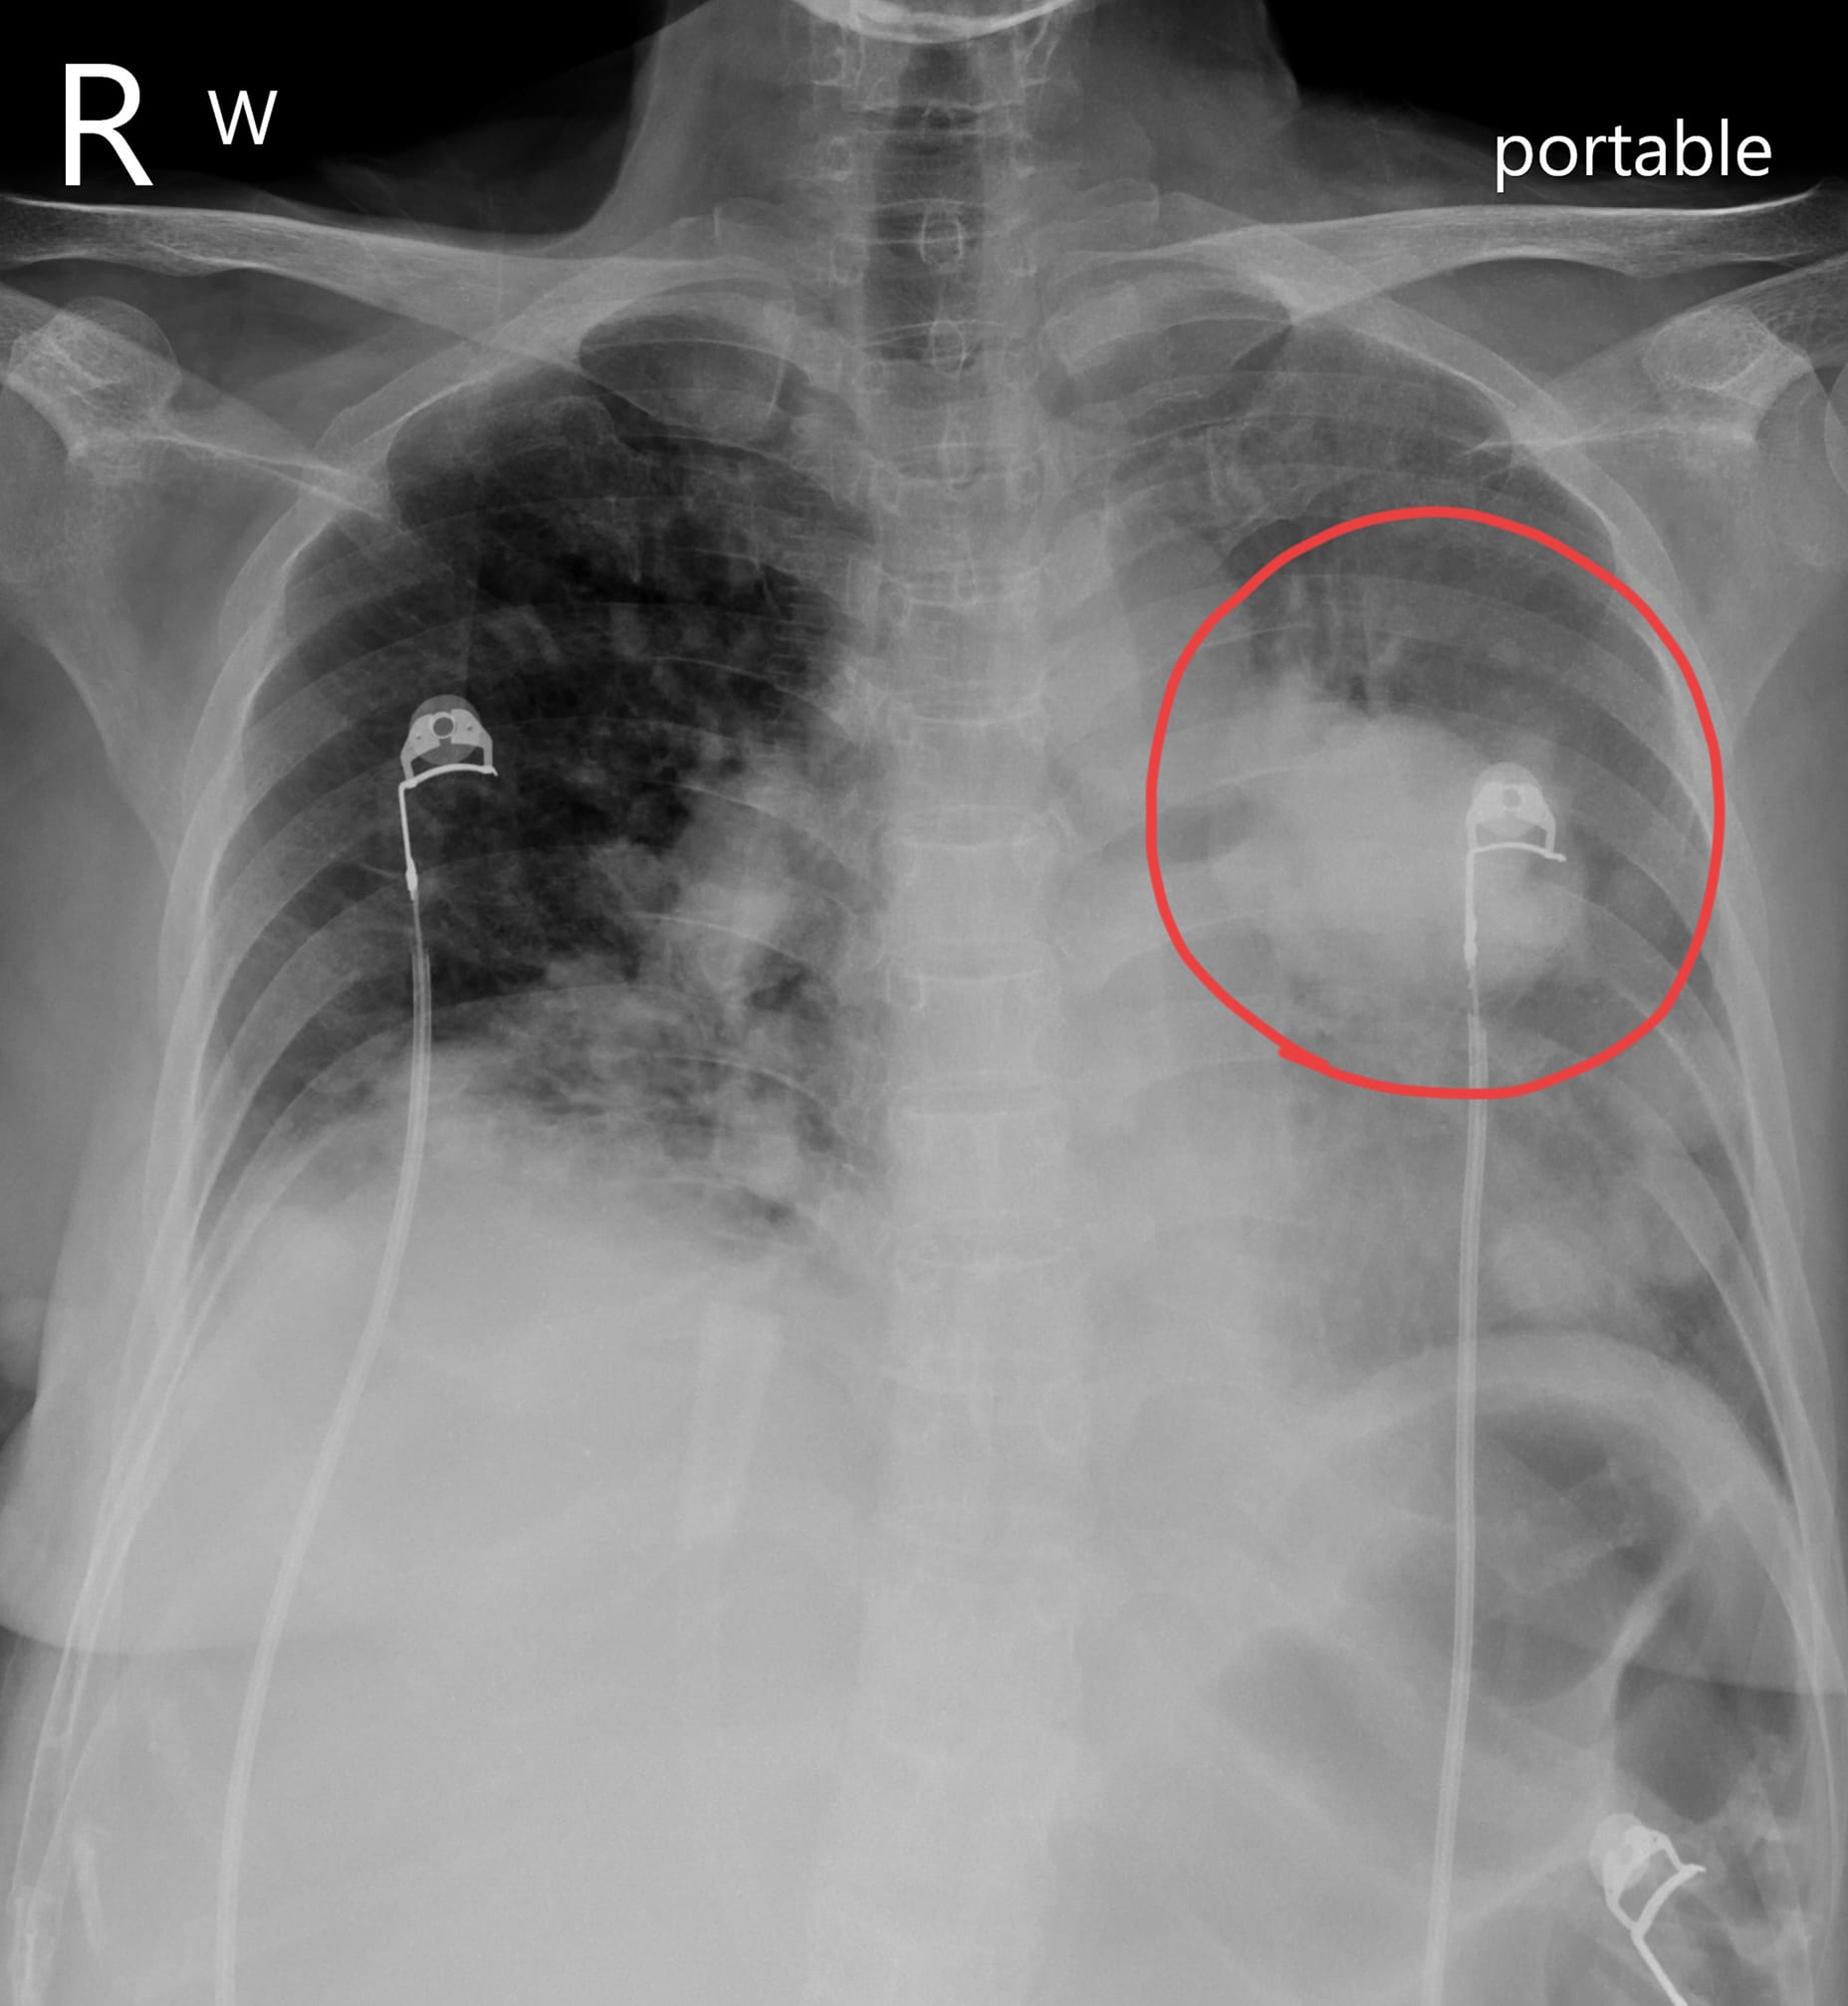

蘇一峰曬出該名病患X光照,指出該名患者病情不樂觀,生命危在旦夕,可能僅剩不到1個月的時間,忍不住嘆就算不菸不酒,若身體出現異狀還是得盡速就醫,千萬別耽誤黃金治療時間,表示倘若早4個月就醫,也許還有許多辦法。